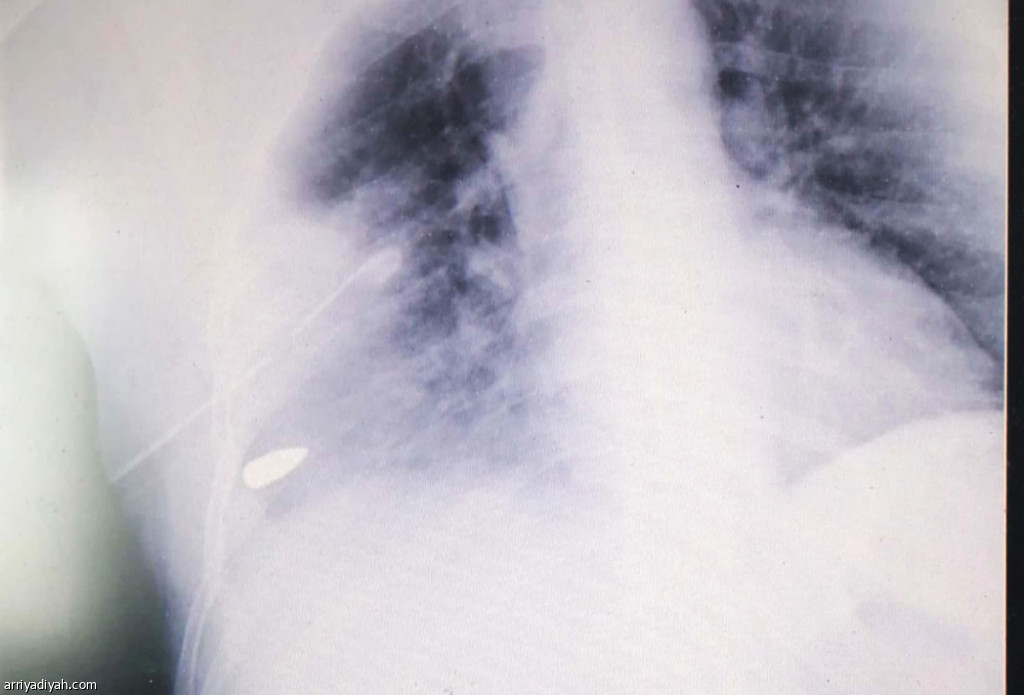

صورة التقطت للأشعة الضوئية التي أجريت لمدرب الشعلة تُظهر استقرار الرصاصة في جسده (خاصة بالرياضية)